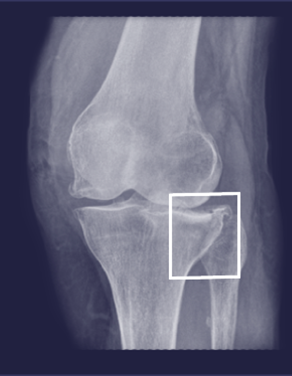

Frakturen automatisch durch künstliche Intelligenz erkennen

Gleamer ist eine künstliche Intelligenz, die Ihnen hilft, Frakturen schneller und sicherer zu erkennen. Durch die automatisierte Befundunterstützung wird sich die Qualität der Diagnosen deutlich verbessern. An arbeitsreichen Tagen passiert es schnell, dass sich eine gewisse Ermüdung bemerkbar macht. Mit Gleamer wird es Ihnen leicht fallen, an solchen Tagen deutlich mehr Röntgenaufnahmen mit Knochenbrüchen zu analysieren. Insgesamt geht die Anzahl übersehener Knochenbrüche um etwa 30 Prozent zurück. Mit einer hohen Zuverlässigkeit wird fast jeder Bruch auf Anhieb sicher erkannt.

Gleamer ist eine künstliche Intelligenz, die Ihnen hilft, Frakturen schneller und sicherer zu erkennen. Durch die automatisierte Befundunterstützung wird sich die Qualität der Diagnosen deutlich verbessern. An arbeitsreichen Tagen passiert es schnell, dass sich eine gewisse Ermüdung bemerkbar macht. Mit Gleamer wird es Ihnen leicht fallen, an solchen Tagen deutlich mehr Röntgenaufnahmen mit Knochenbrüchen zu analysieren. Insgesamt geht die Anzahl übersehener Knochenbrüche um etwa 30 Prozent zurück. Mit einer hohen Zuverlässigkeit wird fast jeder Bruch auf Anhieb sicher erkannt.